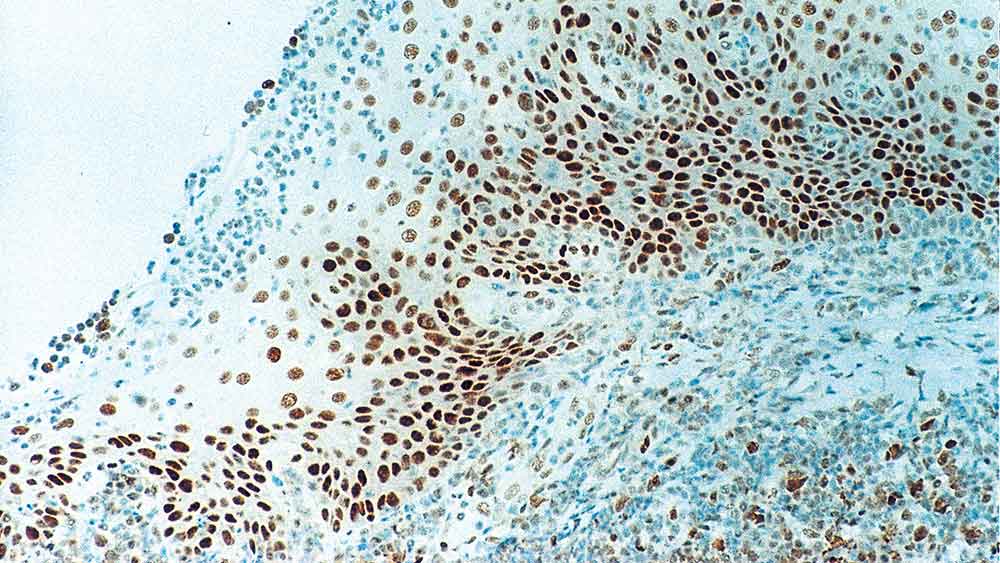

Human tonsil: immunohistochemical staining for Retinoblastoma Gene Protein. Note intense nuclear staining of epithelial cells. Retinoblastoma Gene Protein: clone 13A10

Retinoblastoma (Rb) is a rare tumor of the retina associated with mutations of chromosome 13. The nuclear phosphoprotein encoded by the Rb tumor suppressor gene is present in many cells and may indirectly regulate cell growth by activating the transcription factor ATF-2. Activation of ATF-2 initiates expression of TGF-beta2, which in turn inhibits transcription of genes affecting cell growth. Bilateral mutation of the Rb gene may potentially play a role in the development of a number of malignant tumors.

NCL-L-RB-358 was raised to the N-terminal region of the Rb gene protein.